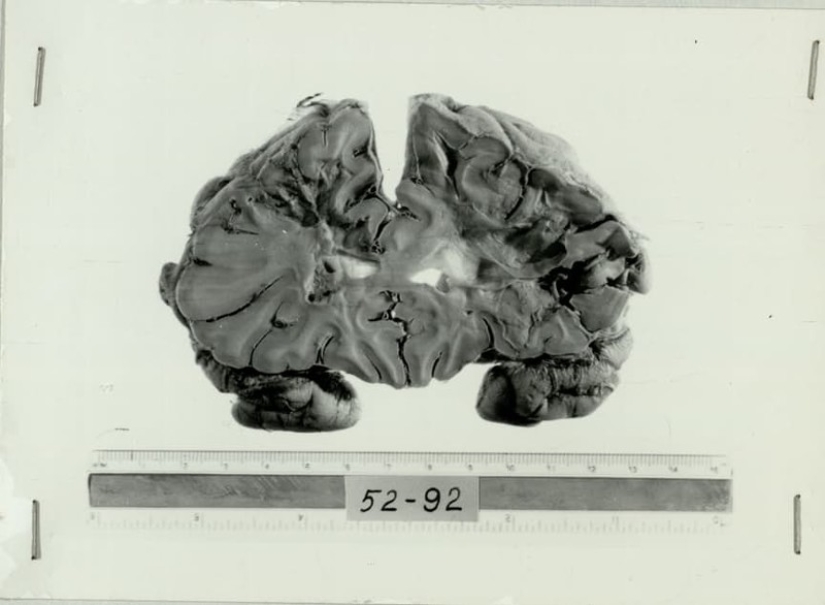

Lobotomy or lakatamia called the operation, during which intentionally injured or have escalas frontal lobe of the brain. Purposely inflicted brain defect broke the connection frontal lobes with the rest of the brain. The doctor injected the knife through the eye socket of the patient, acting almost blindly. The success of the operation depended on the skill of the surgeon, his knowledge of the anatomy of the brain.

Permantaly cortex completes 20 years. The function of this part of the gray matter that make us individual. The frontal lobes provide the coordination, concentration, planning, managing emotions. The set of all functions of the prefrontal cortex creates our personality. The implication was that the lobotomy was turned off this area of the brain, sparing the patient from anxiety, irritability, aggression.